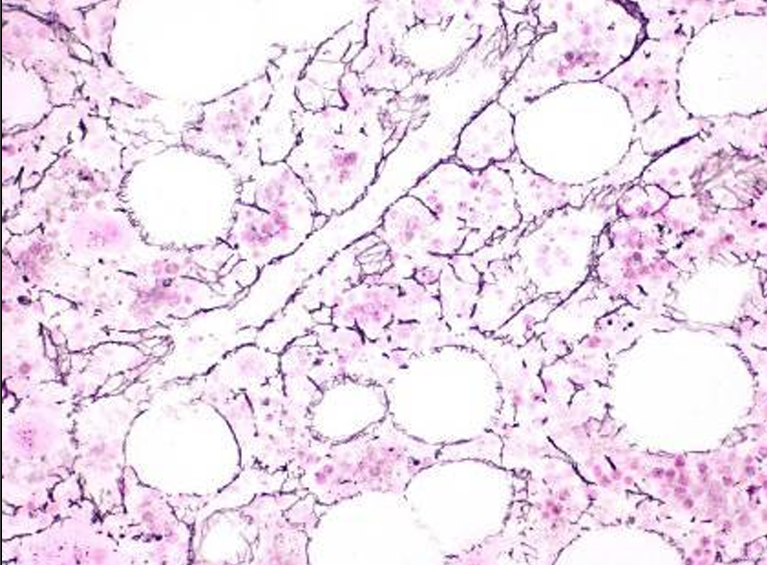

Sinusoides medulares

Célula endotelial

Células reticulares

Adipocitos

Macrófagos medulares

Biopsia médula ósea

Valoración cantidad tejido hematopoyético/tejido adiposo

BIOPSIA MÉDULA OSEA Y ASPIRADO MEDULAR